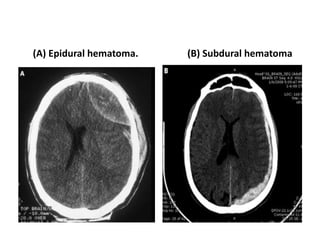

(A) Epidural hematoma. (B) Subdural hematoma

(C) Bilateral contusions with hemorrhage.

(D) Right intraparenchymal hemorrhage with

right to left midline shift. Associated

biventricular hemorrhages.